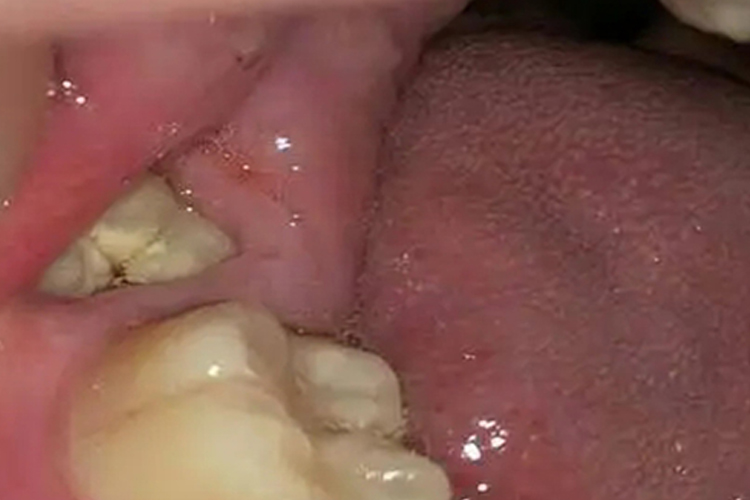

现代人的牙槽骨有不同程度的退化,及智齿本身的退化,可导致智齿萌出异常或者不对称萌出。若下颌智齿存在近中倾斜而与第二磨牙之间有食物嵌塞时,应拔除智齿。若上颌或下颌智齿有一方缺牙,而使相对牙伸长,造成食物嵌塞者,应拔除伸长的牙。其他如多生牙、错位牙等与正常位置的牙间邻接区异常,均可发生食物嵌塞,也应予拔除。